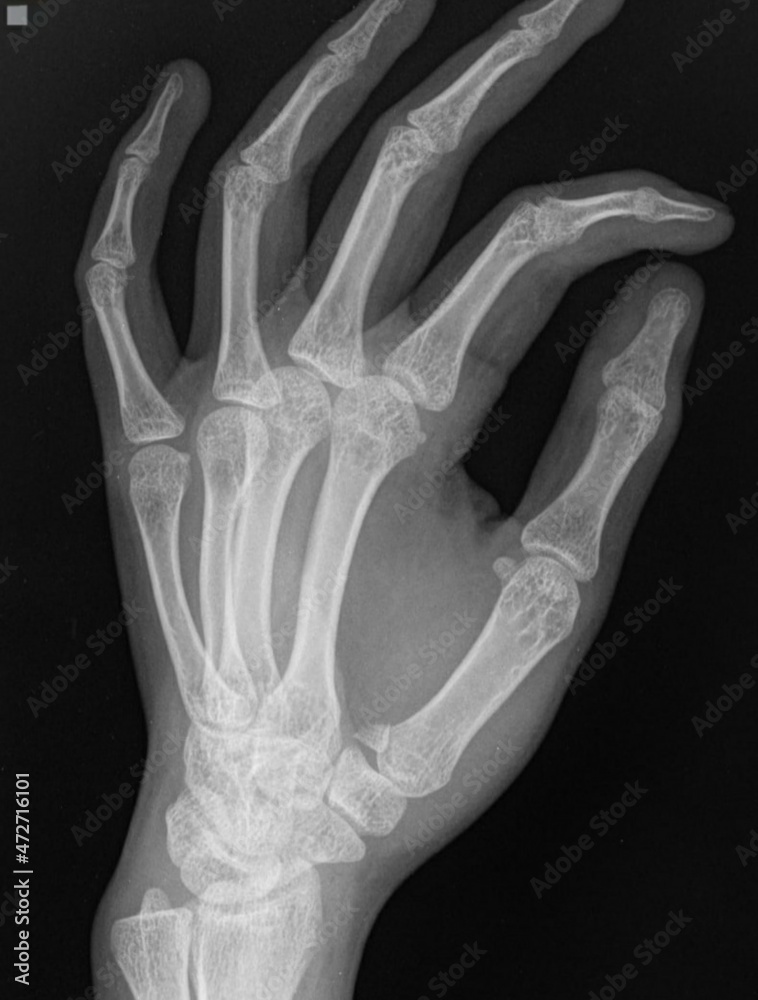

From stock.adobe.com

x ray of human hand,base thumb fracture Stock Photo Basal Thumb Fracture Most thumb bone fractures occur at the base of the first metacarpal, just above the cmc joint. These injuries typically result from an axial load on the thumb with a. If you suspect that you have a broken thumb, you should seek immediate medical help. A thumb fracture is a minor fracture. A thumb fracture is a break in one. Basal Thumb Fracture.